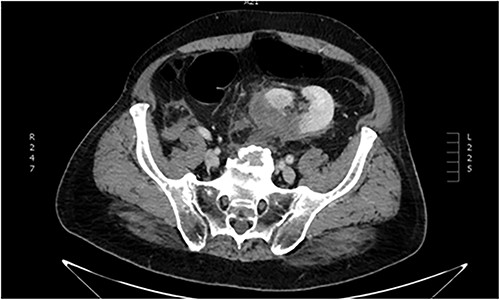

The kidney may be ectopic on its own side (simple ectopia) or across the midline and be fused or unfused with the contralateral kidney (crossed ectopia). The final site of the metanephros determines the location of renal ectopia; the most common position is inside the pelvic cavity, just below the aortic bifurcation [4], as in our case (Fig. 3). Vascular supply is not consistent, and the ectopic kidney may receive vascular access from a range of vessels, such as the iliac, mid sacral or hypogastric arteries [5]; understanding this anatomy, thus, is essential for any surgeon operating on a patient with an ectopic kidney.

Anatomic illustration. Location of the pelvic kidney below the aortic bifurcation.